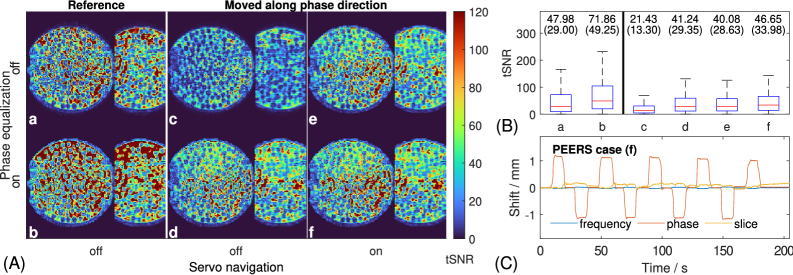

Figure 8 shows a tSNR comparison for an in-vivo case with instructed motion after realignment. With motion, the mean tSNR drops from about 50 (a; reference) to 39 (c). The mean tSNR increases to 42 for phase equalization alone (d) and to 45 for servo navigation alone (e), while reaching 50 for PEERS, which includes both corrections (f). Still, the corrected motion case does not achieve the tSNR performance of 63 of the motion-free case with phase equalization. If motion is present, the relative importance of the run-time motion correction thus increases. The in-vivo results are supported by phantom data shown in Supporting Figure S1, where the phantom was placed on a platform and shifted in and out by 1mm1\,\mathrm{mm} every 10 seconds. The shifting direction was aligned with the frequency, phase and slice direction in separate scans.

Figure 8: In-vivo tSNR example with instructed motion comparing the performance of servo navigation and phase equalization after realignment. (A) tSNR images without (a-b) and with (c-f) motion. (B) Associated tSNR boxplots with mean (median) values. (C) Navigator-based rotation parameters for Servo on. The boxplots show a clear tSNR reduction by motion without servo navigation and phase equalization (c). With motion, the servo navigation contributes higher tSNR gains than phase equalization, although both consistently improve tSNR.